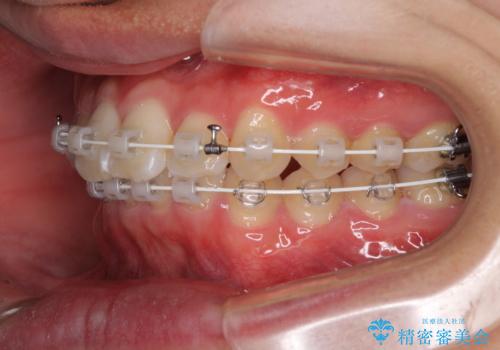

深い咬み合わせとデコボコ ワイヤー矯正で短期治療

- 審美装置

インビザラインでの治療も可能でしたが、深い咬み合わせと奥歯の咬み合わせを改善するにあたり、ワイヤー矯正の方が治療期間を短縮できると判断し、ワイヤー矯正をお勧めしました。

結果として、1年かからずに奥歯の咬み合わせを改善することができました。